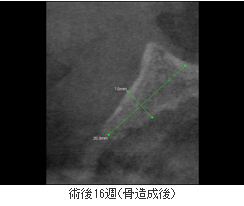

術前の写真のように骨の量が足りないと、インプラント手術ができません。

このような場合、いままではあごのほかの部分から骨を切り取り移植して骨を増やしました。そのため強い痛みやはれを伴いました。

PRGF ENDRETシステムにより、わずか16週後にしっかりしたあごの骨ができ、インプラントが可能になりました。